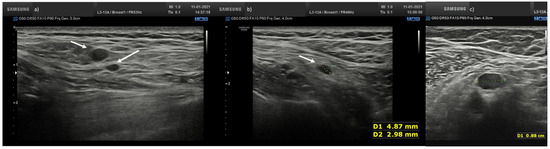

A total of 25 (43.1%) nodes showed eccentric cortical thickening with wide echogenic hilum and oval shape (Figure 1 and Figure 2).

Figure 2.

Axillary lymph node with eccentric asymmetric cortical thickening with wide echogenic hilum and oval shape.

Overall, 19 nodes (32.8%) showed asymmetric eccentric cortical thickening with wide echogenic hilum and oval shape (Figure 3).

Figure 3.

Lymph node (arrow) with asymmetric eccentric concentric cortical thickening in laterocervical side with reduction in the width of the echogenic hilum and oval shape.

A total of 10 nodes (17.2%) showed concentric cortical thickening with reduction in the width of the echogenic hilum and oval shape (Figure 1b).